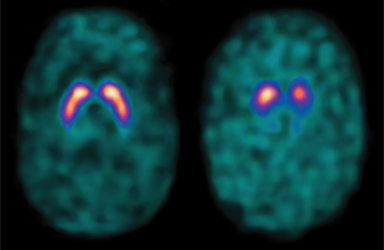

• Normal DaTscan™ (left image) shows two symmetric comma- or crescent-shaped regions in the middle of the brain. For a patient with tremor, this finding often leads to an essential tremor diagnosis.

• Abnormal DaTscan™ (right image) may include any of the following characteristics: left/right asymmetry, more circular or oval shapes, or faint dopamine activity. An abnormal DaTscan™ indicates a deficiency of dopamine—a sign of Parkinson’s disease or other primary Parkinsonian syndromes.